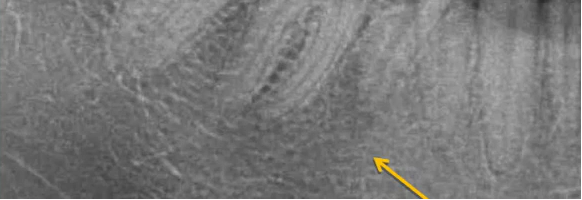

下图可看到,左上4根方有低密度影,牙冠非常完整,首先可以考虑是上颌骨的间隔而不是根尖周囊肿。

曲面断层片怎么看口腔精读 | 一次性教你看懂曲面断层片!_https://www.jmylbn.com_新闻资讯_第10张

(解剖结构辨认)